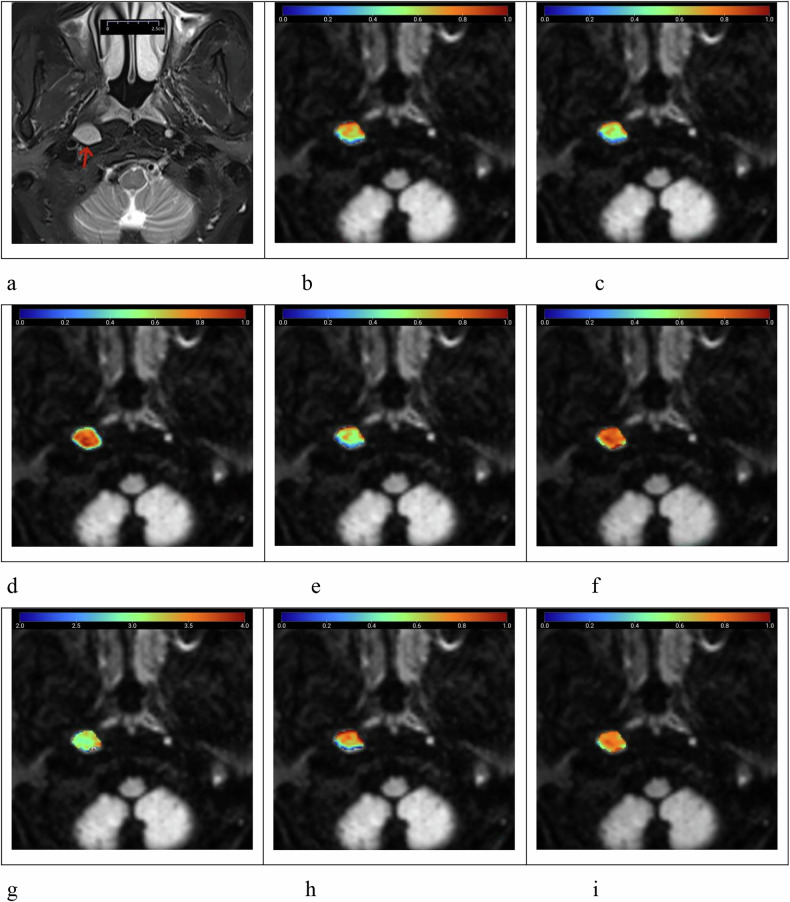

Methods: Fifty-nine patients with 68 RLNs (23 benign and 45 metastatic) were enrolled. All patients underwent DWI with 12 b-values. Diffusion data were reconstructed using conventional DWI, SEM, FROC, and CTRW models, yielding nine parameters: apparent diffusion coefficient (ADC), distributed diffusion coefficient (DDC)SEM, αSEM, DFROC, βFROC, μFROC, DCTRW, αCTRW, and βCTRW. Diffusion parameters and morphological features were compared using Mann-Whitney U, independent sample t, or χ2 tests. Logistic regression analysis was performed to identify the best diffusion indicator for classification and to develop a multiparameter model combining morphological features. Area under the receiver operating curve (AUC) and DeLong tests were used.

Results: Significant differences in diffusion parameters were found between benign and metastatic RLNs, except for αCTRW (p ≤ 0.022). Benign RLNs exhibited higher ADC, DDCSEM, DFROC, and DCTRW, while metastatic RLNs had higher αSEM, βFROC, μFROC, and βCTRW. Multivariate logistic regression analysis identified βCTRW as the optimal single diffusion indicator (AUC = 0.913). The combined model of βCTRW with morphological features further improved diagnostic performance and yielded an AUC of 0.948.